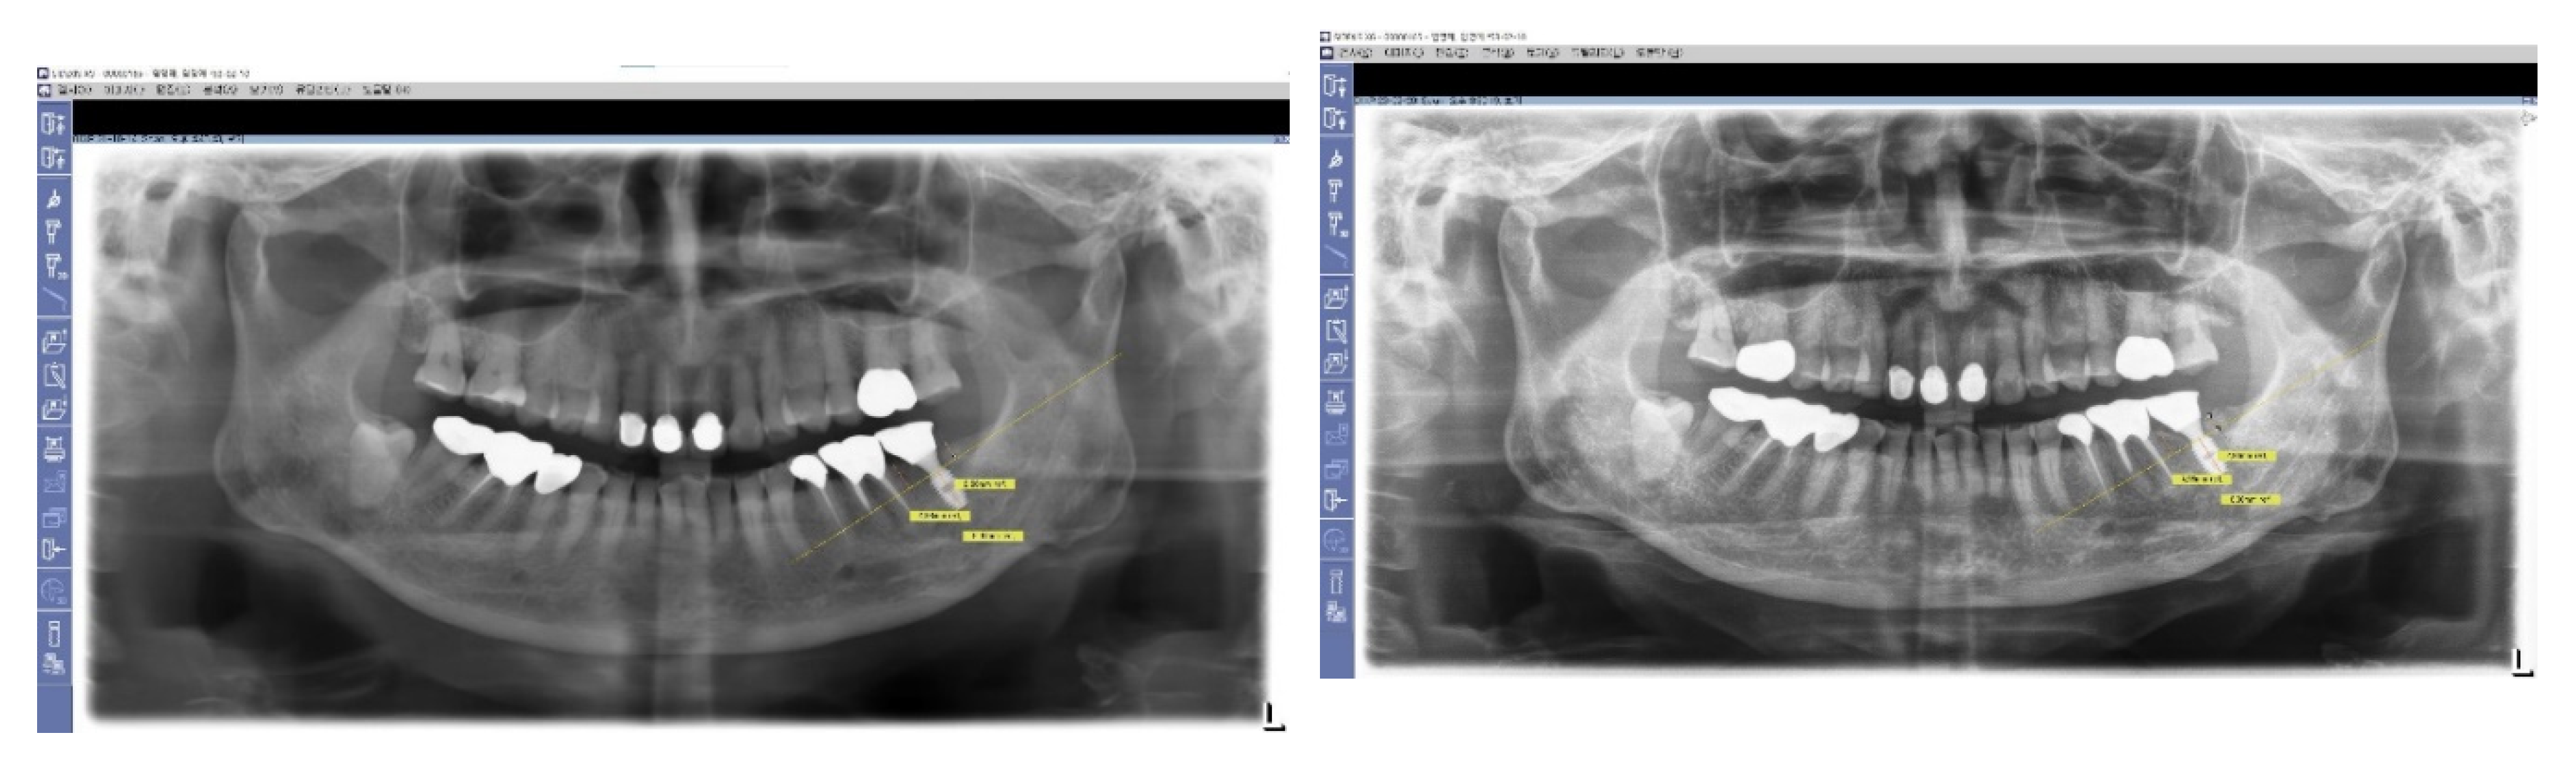

Typically, a plain X-ray (panoramic view, or standard oral) is recommended for routine follow-up examinations to assess the outcomes of implant placements. However, using plain X-rays to observe the depth of an implant fixture and to study its relationship with surrounding tissues (bone and soft tissue) is limited, as this imaging modality only provides information on the mesiodistal relationship. Occasionally, while plain X-rays may indicate that implant fixtures are placed very deep, further examination using Cone Beam Computed Tomography (CBCT) can reveal that the buccal depth of implant placement is actually epi-crestal.

In this study, images from CBCT reviews were utilized for a 3-dimensional analysis to investigate not only the mesiodistal aspects but also the buccal and lingual sides, examining the relationship between the artificial implant complex (implant fixture, abutment, and crown) and the biological tissues (bone and soft tissue).

Figure 7. Long-Term Stability of Lower First Implants. This figure displays a panoramic view X-ray taken in 2023, showing the stable results of both lower first implants that were placed in 2012. These implants, which utilize Subcrestally Placed Implants (SPI) with Internal Platform Switching (IPS) design (specifically Bicon implants), demonstrate long-term stability and successful integration.

Preprints 103958 g007